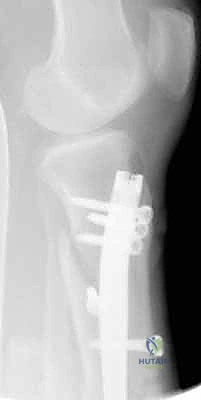

- التثبيت التشابكي (Interlocking): يتم تمرير مسامير صغيرة عرضية عبر العظم والمسمار النخاعي في الطرفين العلوي والسفلي، مما يمنع دوران العظم حول المسمار ويحافظ على طول الساق الطبيعي بدقة متناهية.

4. إدخال المسمار النخاعي والتثبيت النهائي

يتم تمرير مسمار التيتانيوم بدقة داخل العظم. وبمجرد التأكد من موضعه المثالي بالأشعة، يقوم البروفيسور هطيف بإدخال المسامير التشابكية (Locking Screws) العرضية في أعلى وأسفل المسمار لضمان التثبيت المطلق.